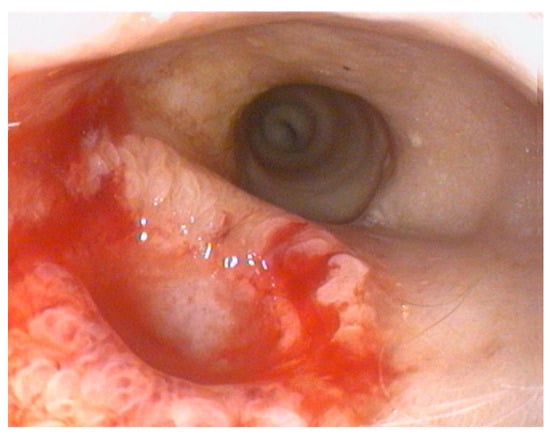

The endoscopy demonstrated complete resolution of the duodenal mass, which was replaced by a well- demarcated focal mucosal depression at the site of the previous lesion (Figure 3).

Endoscopic biopsies collected from this area revealed coalescent villi with thickened and edematous apices, without damage to the surface epithelium. Occasional glandular dilatation was observed, indicating mild epithelial injury. No lymphatic vessel dilation was present. Mucosal fibroplasia was mild. The number of intraepithelial lymphocytes was within normal limits, while the lamina propria showed moderate infiltration of lymphocytes and plasma cells, along with a mild increase in neutrophils. These findings were interpreted as consistent with a moderate chronic- active lymphoplasmacytic and neutrophilic enteritis with mild fibroplasia, suggestive of a post- inflammatory reparative phase, consistent with the resolution of previously diagnosed FGESF (Figure 4).

Figure 3. Endoscopic view showing mucosal depression.